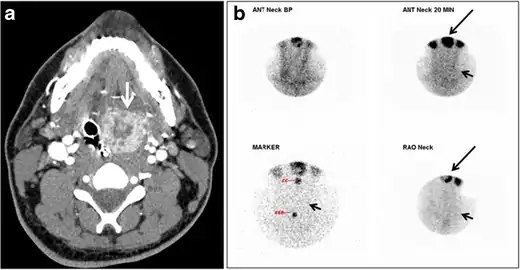

CT scan and scintigraphy images of lingular ectopic thyroid

An ectopic thyroid, also called accessory thyroid gland, is a form of thyroid dysgenesis in which an entire or parts of the thyroid located in another part of the body than what is the usual case. A completely ectopic thyroid gland may be located anywhere along the path of the descent of the thyroid during its embryological development, although it is most commonly located at the base of the tongue, just posterior to the foramen cecum of the tongue. In this location, an aberrant or ectopic thyroid gland is known as a lingual thyroid.[3] If the thyroid fails to descend to even higher degree, then the resulting final resting point of the thyroid gland may be high in the neck, such as just below the hyoid bone.[3] Parts of ectopic thyroid tissue ("accessory thyroid tissue") can also occur, and arises from remnants of the thyroglossal duct, and may appear anywhere along its original length.[3] Accessory thyroid tissue may be functional, but is generally insufficient for normal function if the main thyroid gland is entirely removed.[3]